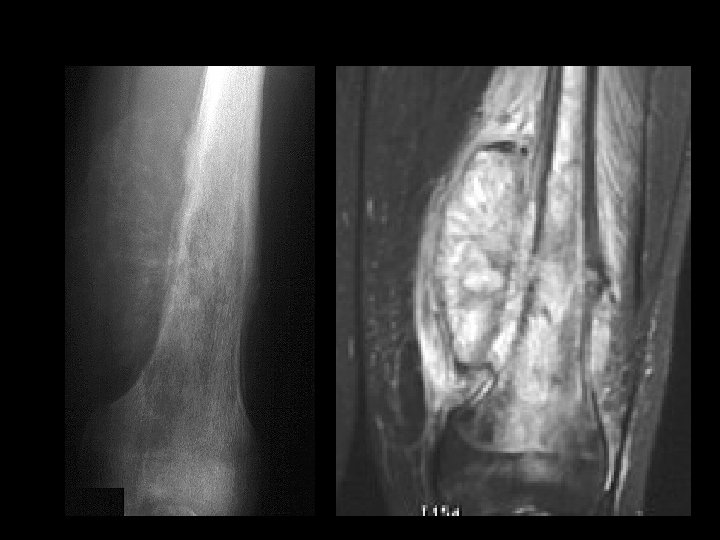

A 14 year old boy presents with pain and a mass above the knee. Take a look at the AP and lateral radiographs first.

Cross-sectional imaging Pictures are pretty, but diagnosis • established at histology MRI best for most tumors • optimal results at sites with experience – Role of CT limited • may assist in assessing tumor matrix – useful in directing biopsy –